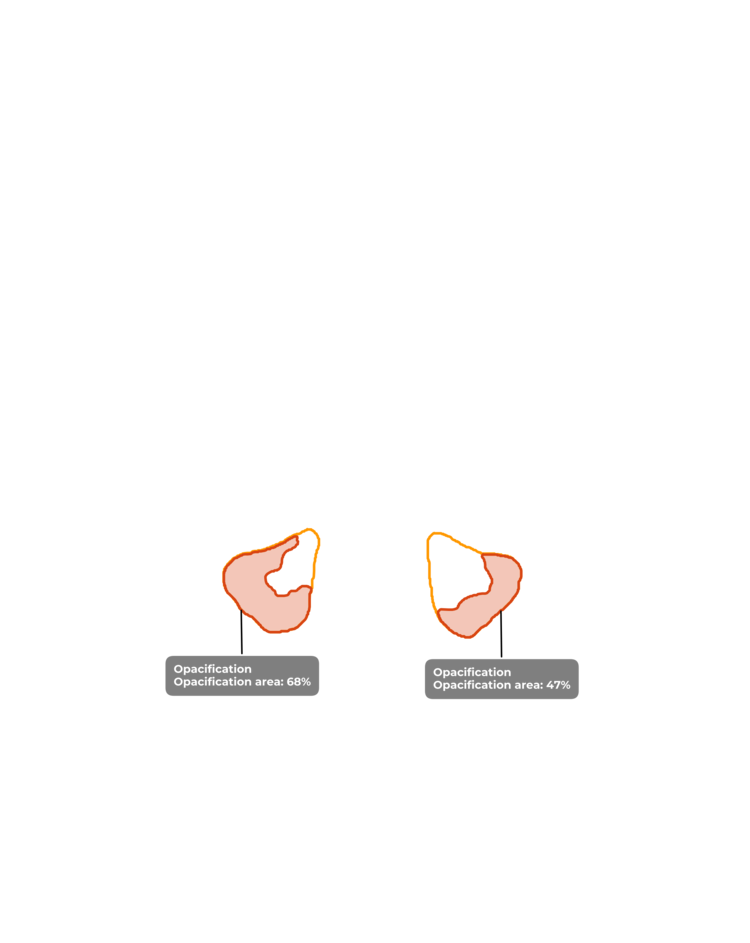

ИИ и умные алгоритмы для анализа рентгеновских снимков черепа. Обнаружение синусита и процента заполненности пазух носа менее чем за 30 секунд